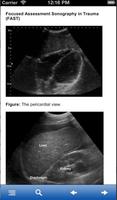

التقييم المركز الصدمة التصوير بالموجات فوق الصوتية